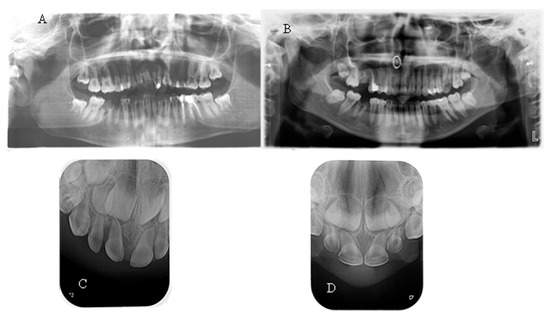

No taurodontism was detected when comparing the panoramic X-rays of hypophosphatemic children with those of healthy patients. In most of them, a normal thickness of the root dentin was observed. When comparing a periapical radiograph of the upper anterior region of a child with a primary dentition and hypophosphatemia due to a central incisor trauma with a similar X-ray of a healthy child of the same age, significantly wider pulp chambers and a thin layer of coronal and root dentin were noted (Figure 3). This symptom was observed in 27.27% of the children examined in this study.

Figure 3. (A) OPG of a 15-year-old girl with XLH; (B) OPG of a healthy 15-year-old girl; (C) Periapical X-ray of a 3-year-old boy with XLH; (D) Periapical X-ray of a 3-year-old healthy boy.

The spontaneous endodontic infections described in the literature were found in two of the examined children (18.8%). The first child, a 17-year-old girl, reported pain and swelling in the lower anterior region about a year ago, which was treated with antibiotics since no apparent cause was found after a visit to the dentist. There were no complaints at the time of the examination; the dentition was intact, and the mucosa and gingiva were normal. When performing a cold test, tooth 41 did not react. On a periapical X-ray, a large periapical lesion was observed in tooth 41 (Figure 4). The unusual anatomy of the coronal pulp of the anterior teeth, which had several pulp horns, extended towards the incisal edge, was striking. The girl had previously been treated with burosumab, but the treatment was interrupted at the request of the family and is about to be restarted.

Figure 4. (A) Intraoral image of a 17-year-old girl with XLH; (B) Intraoral X-ray of the same girl with visible necrosis of an anterior teeth without previous trauma history; (C) Intraoral X-ray of a 2.5-year-old girl with XLH. Thinner radicular dentin is clearly visible.

The second child, 2.5 years old, was brought in by the mother, who had noticed a fistula in the lower frontal area. The mother reported no history of trauma. Upon clinical examination, a vestibular fistula was observed in the apical region of tooth 81, which appeared intact. The sectional radiograph revealed periapical radiolucency and delayed root development of tooth 81 compared with tooth 71, indicating pulp necrosis (Figure 4). The radiograph also showed a thin layer of dentin on all the frontal teeth, particularly in the root area, along with wide pulp chambers and root canals. The child has not yet begun treatment for the general condition.